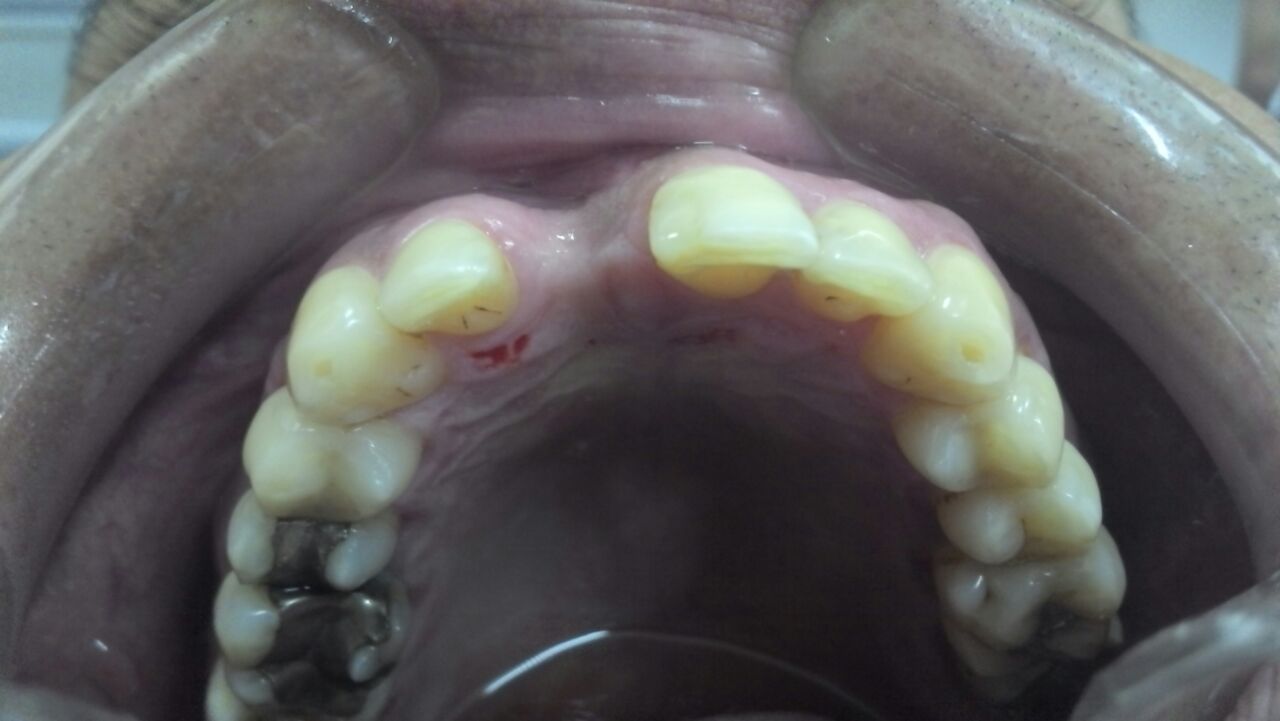

Veja esse mesmo caso com uma vista oclusal.

Percebam como o osso perdeu espessura. Há uma depressão, um grande defeito ósseo na região do dente perdido.

Como colocar um implante nessa situação? Ainda que se possa instalar o implante, a prótese não ficará adequada, esteticamente perfeita. O resultado será péssimo.